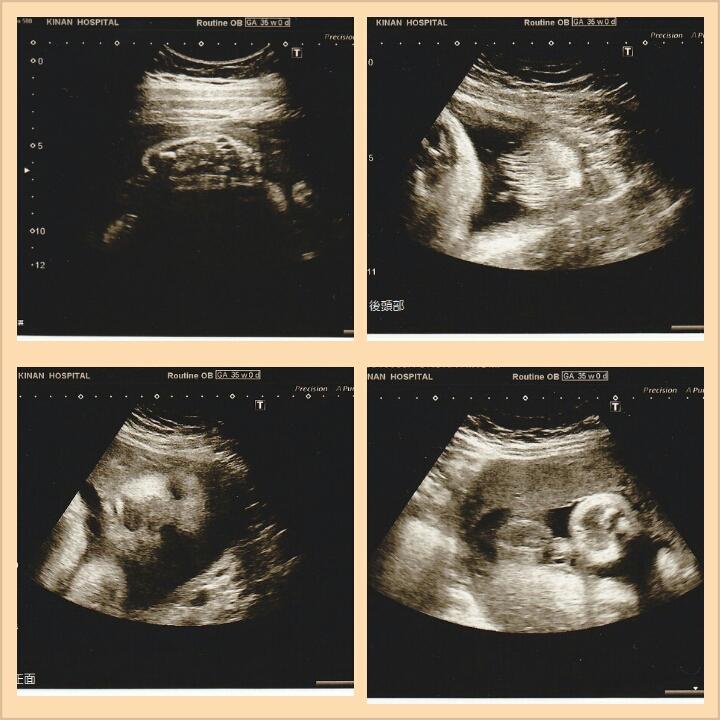

出産先の病院で、胎児超音波検査を受けました♪

30分かけて、かなり詳しく見てくれ、楽しかったぁ�・

足裏は、7cmと、大きさまでわかるみたい♪